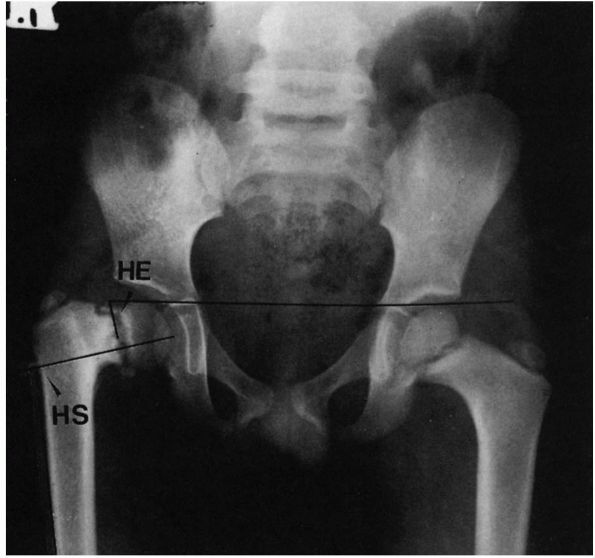

institute treatment so that normal development may occur. If the hip

remains completely dislocated, its natural history depends on two

factors: the presence or absence of a false acetabulum and

bilateralness.

complete dislocations do well, maintaining a good range of motion and

little functional disability. Completely dislocated hips with

well-developed false acetabuli, however, are more likely to develop

degenerative joint disease in the false acetabulum and have a poor

clinical result (Figure 15-6). Degenerative

joint disease in the false acetabulum usually occurs in the fourth and

fifth decades of life. In bilateral complete dislocations, lower-back

pain may occur. This may be secondary to the hyperlordosis of the

lumbar spine associated with the hip flexion adduction deformities

caused by the dislocations.

![]() |

|

FIGURE 15-6.

Radiograph of a 43-year-old woman with complete dislocation of both hips. She has no symptoms on the right but has disabling symptoms from the left hip. She has no false acetabulum on the right but has a well-developed false acetabulum on the left with secondary degenerative changes present. (Weinstein SL. Natural history of congenital hip dislocation [DDH] and hip dysplasia. Clin Orthop 1987;225:62-76) |